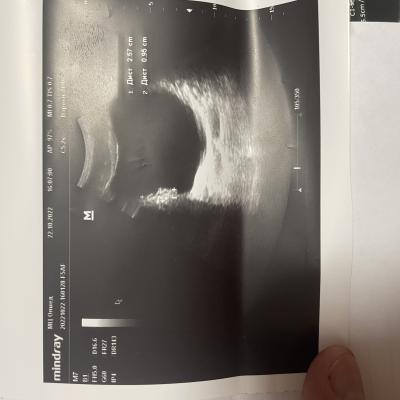

Здравствуйте, болят яички 1.5 года. 6 месяцев режет при мочеиспускании, боли в копчике (начинается с копчика, в течение дня усиливаются, поднимаются выше боли). Может ли это быть из-за мочевого пузыря? Фото прикрепил, там есть образование некое. Бак посев мочи отриц, эр, лейк. в норме, зппп отриц, в секрете простаты клебсиела, кровь в норме, млча в норма. Мрт поясницы делал, невролог сказал, что боли точно не из-за невролгии.

Добрый день! Вам нужно выполнить МРТ малого таза - там будет видно образование в стенке мочевого пузыря (если оно действительно есть). После этого надо обратиться к онкоурологу для интерпретации результатов МРТ и решения вопроса о дальнейшей тактике. Удачи.